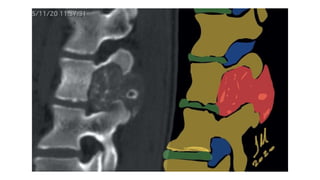

Los ABC espinales suelen mostrar una marcada remodelación expansiva (►Fig. 5). Aunque

centrado en los elementos posteriores, 75 a 90% de los casos se extienden hacia el cuerpo

vertebral.

La tomografía computarizada y la resonancia magnética de un ABC primario muestran una o más

comúnmente, múltiples niveles de líquido que representan hemorragia con sedimentación.18 Durante

la obtención de imágenes de sección transversal, puede ser necesario colocar su pino durante 10

minutos para detectar niveles de líquidos.

La resonancia magnética también es indispensable para determinar la extensión de la lesión y la

relación con el canal central y raíces nerviosas, como en todos los tumores espinales.

Metahemoglobina dentro de los componentes del fluido muestran un aumento de señal en ambos

Imágenes de RM potenciadas en T1 y potenciadas en T2. Un bajo El borde de intensidad de la señal

en todas las secuencias de pulsos corresponde a un membrana perióstica intacta y a menudo

engrosada borde delgado